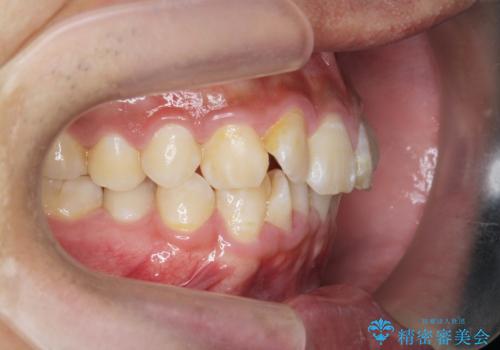

遠心移動を伴うマウスピース非抜歯矯正治療

- 「前歯の見た目を改善したい。」と矯正治療を希望され来院されました。

前歯のガタつきに加え、上顎が前にある咬合関係(上顎前突)を改善すべく、マイクロインプラントを用いた上顎奥歯の後方移動、拡大、ディスキングを用いたマウスピース矯正治療を計画します。

マイクロインプラントを使用したことで、しっかりと遠心移動が為され、良好な咬合関係が達成されました。